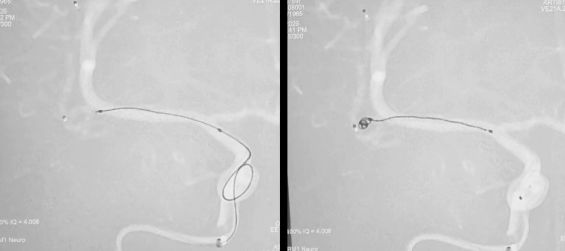

3. 通路搭建,导管到位

微导丝超选、支架导管到位

4. 致密填塞,稳定成篮

栓塞导管到位、弹簧圈逐步填塞

5. 支架释放,精准贴壁

支架释放